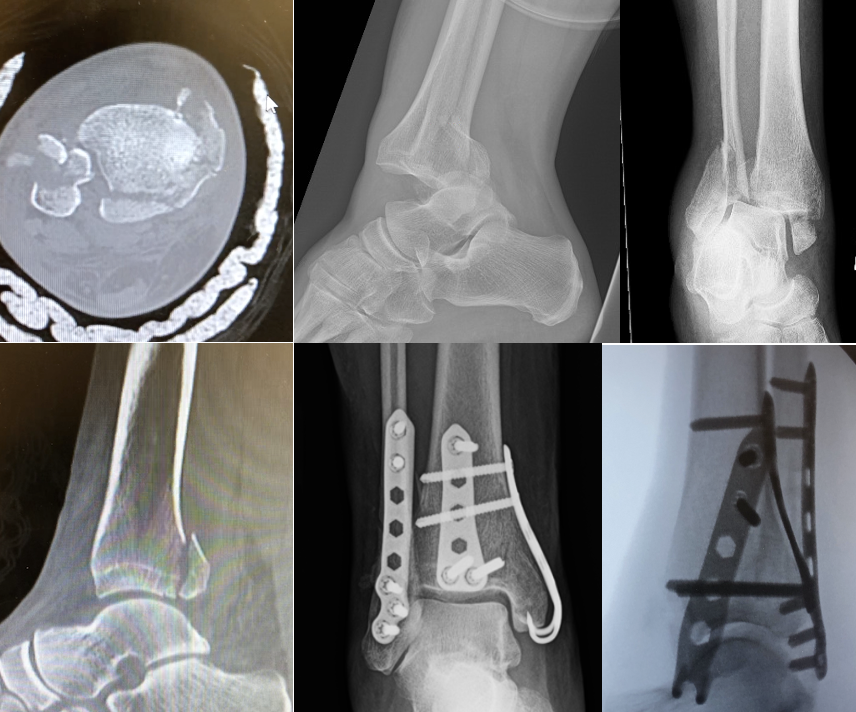

Posterior malleolus fracture Image

From radiopaedia.org

Posterior malleolus fracture Image Posterior Malleolus Fracture Splint The most stable splint is the stirrup plus posterior. stabilising lateral or medial fractures inherently improves posterior fragment stability in these patients. there are three main splinting options for the ankle. learn about the anatomy, classification, and treatment of lateral malleolus fractures, which are common. ankle fractures are one of the most common lower extremity injuries. Posterior Malleolus Fracture Splint.